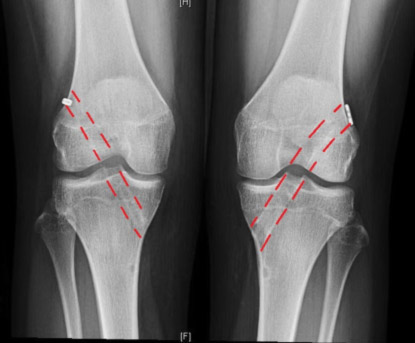

ACL Tear (Left) and ACL Construction (Right)

Post-operative X-rays of the tunnels in a patient with bilateral ACL reconstructions done by Dr. Ahmad.